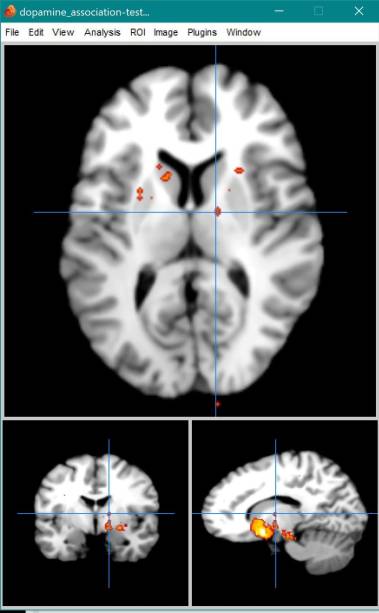

Neurosynth Map for Dopamine

Reverse inference maps in NeuroSynth with search terms (a) reward and… (n.d.). Retrieved February 18, 2019, from https://www.researchgate.net/figure/Reverse-inference-maps-in-NeuroSynth-with-searc h-terms-a-reward-and-b-dopaminergic_fig2_284786249

Neurosynth Coordinate Associations

| Individual voxel | Seed-based network | |||

|---|---|---|---|---|

| Name | z-score | Posterior prob. | Func. conn. ® | Meta-analytic coact. ® |

| **ventral tegmental** | 20.53 | 0.96 | 0.37 | 0.63 |

| tegmental | 20.38 | 0.96 | 0.37 | 0.62 |

| midbrain | 14.34 | 0.92 | 0.43 | 0.6 |

| **substantia** | 13.11 | 0.94 | 0.38 | 0.67 |

| reward | 11.42 | 0.85 | 0.25 | 0.47 |

| **dopaminergic** | 8.87 | 0.88 | 0.27 | 0.57 |

| periaqueductal | 8.38 | 0.91 | 0.27 | 0.35 |

| **striatum** | 7.91 | 0.8 | 0.22 | 0.4 |

| **monetary** | 7.29 | 0.84 | 0.16 | 0.38 |

| **nucleus** | 6.89 | 0.79 | 0.32 | 0.46 |